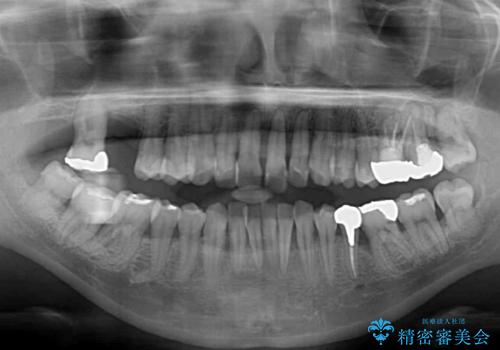

- かかりつけ医にて歯周病治療の名目で治療を行っていたものの、治療プランが明確でないままにインプラント処置を行うとことに疑問を感じ、来院された患者様です。

かかりつけ医では、歯周病治療は終了したため、抜歯を行った右上奥歯にインプラント埋入を行うとの案内があったそうです。

検査を行ったところ、歯周外科処置や抜歯が必要と思われる箇所が散見されたため、あらためて当院に歯周病の初期治療から行うこととしました。

下顎前歯の叢生も気になっており、矯正治療も並行して進めていくこととしました。